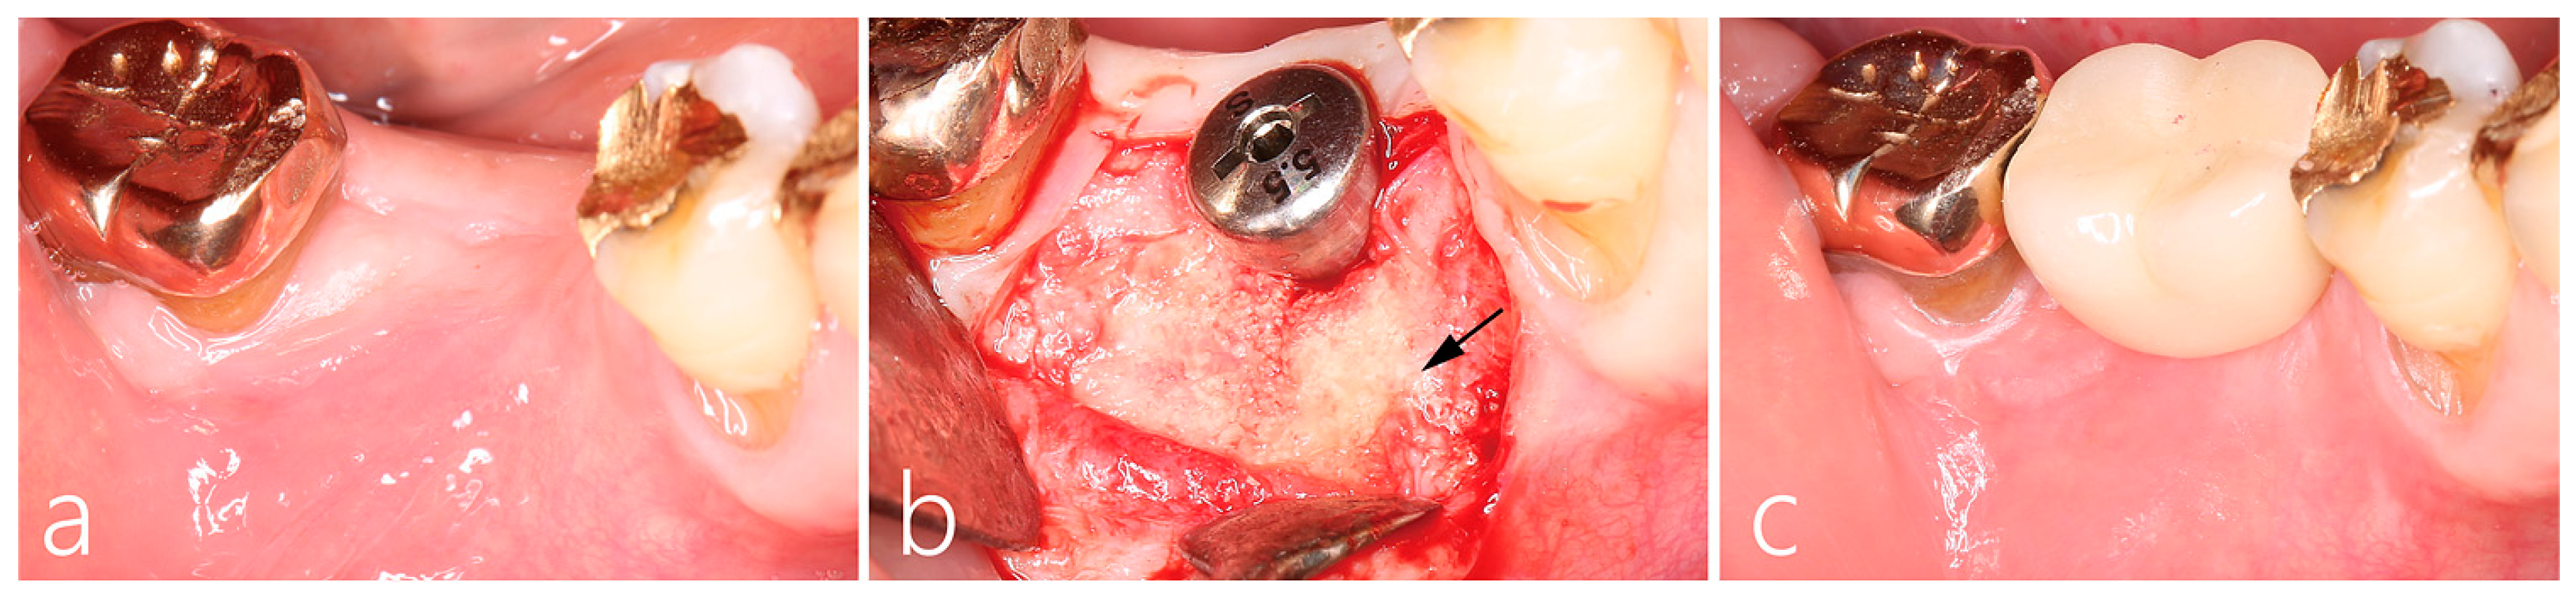

2.4. Surgical Reentry